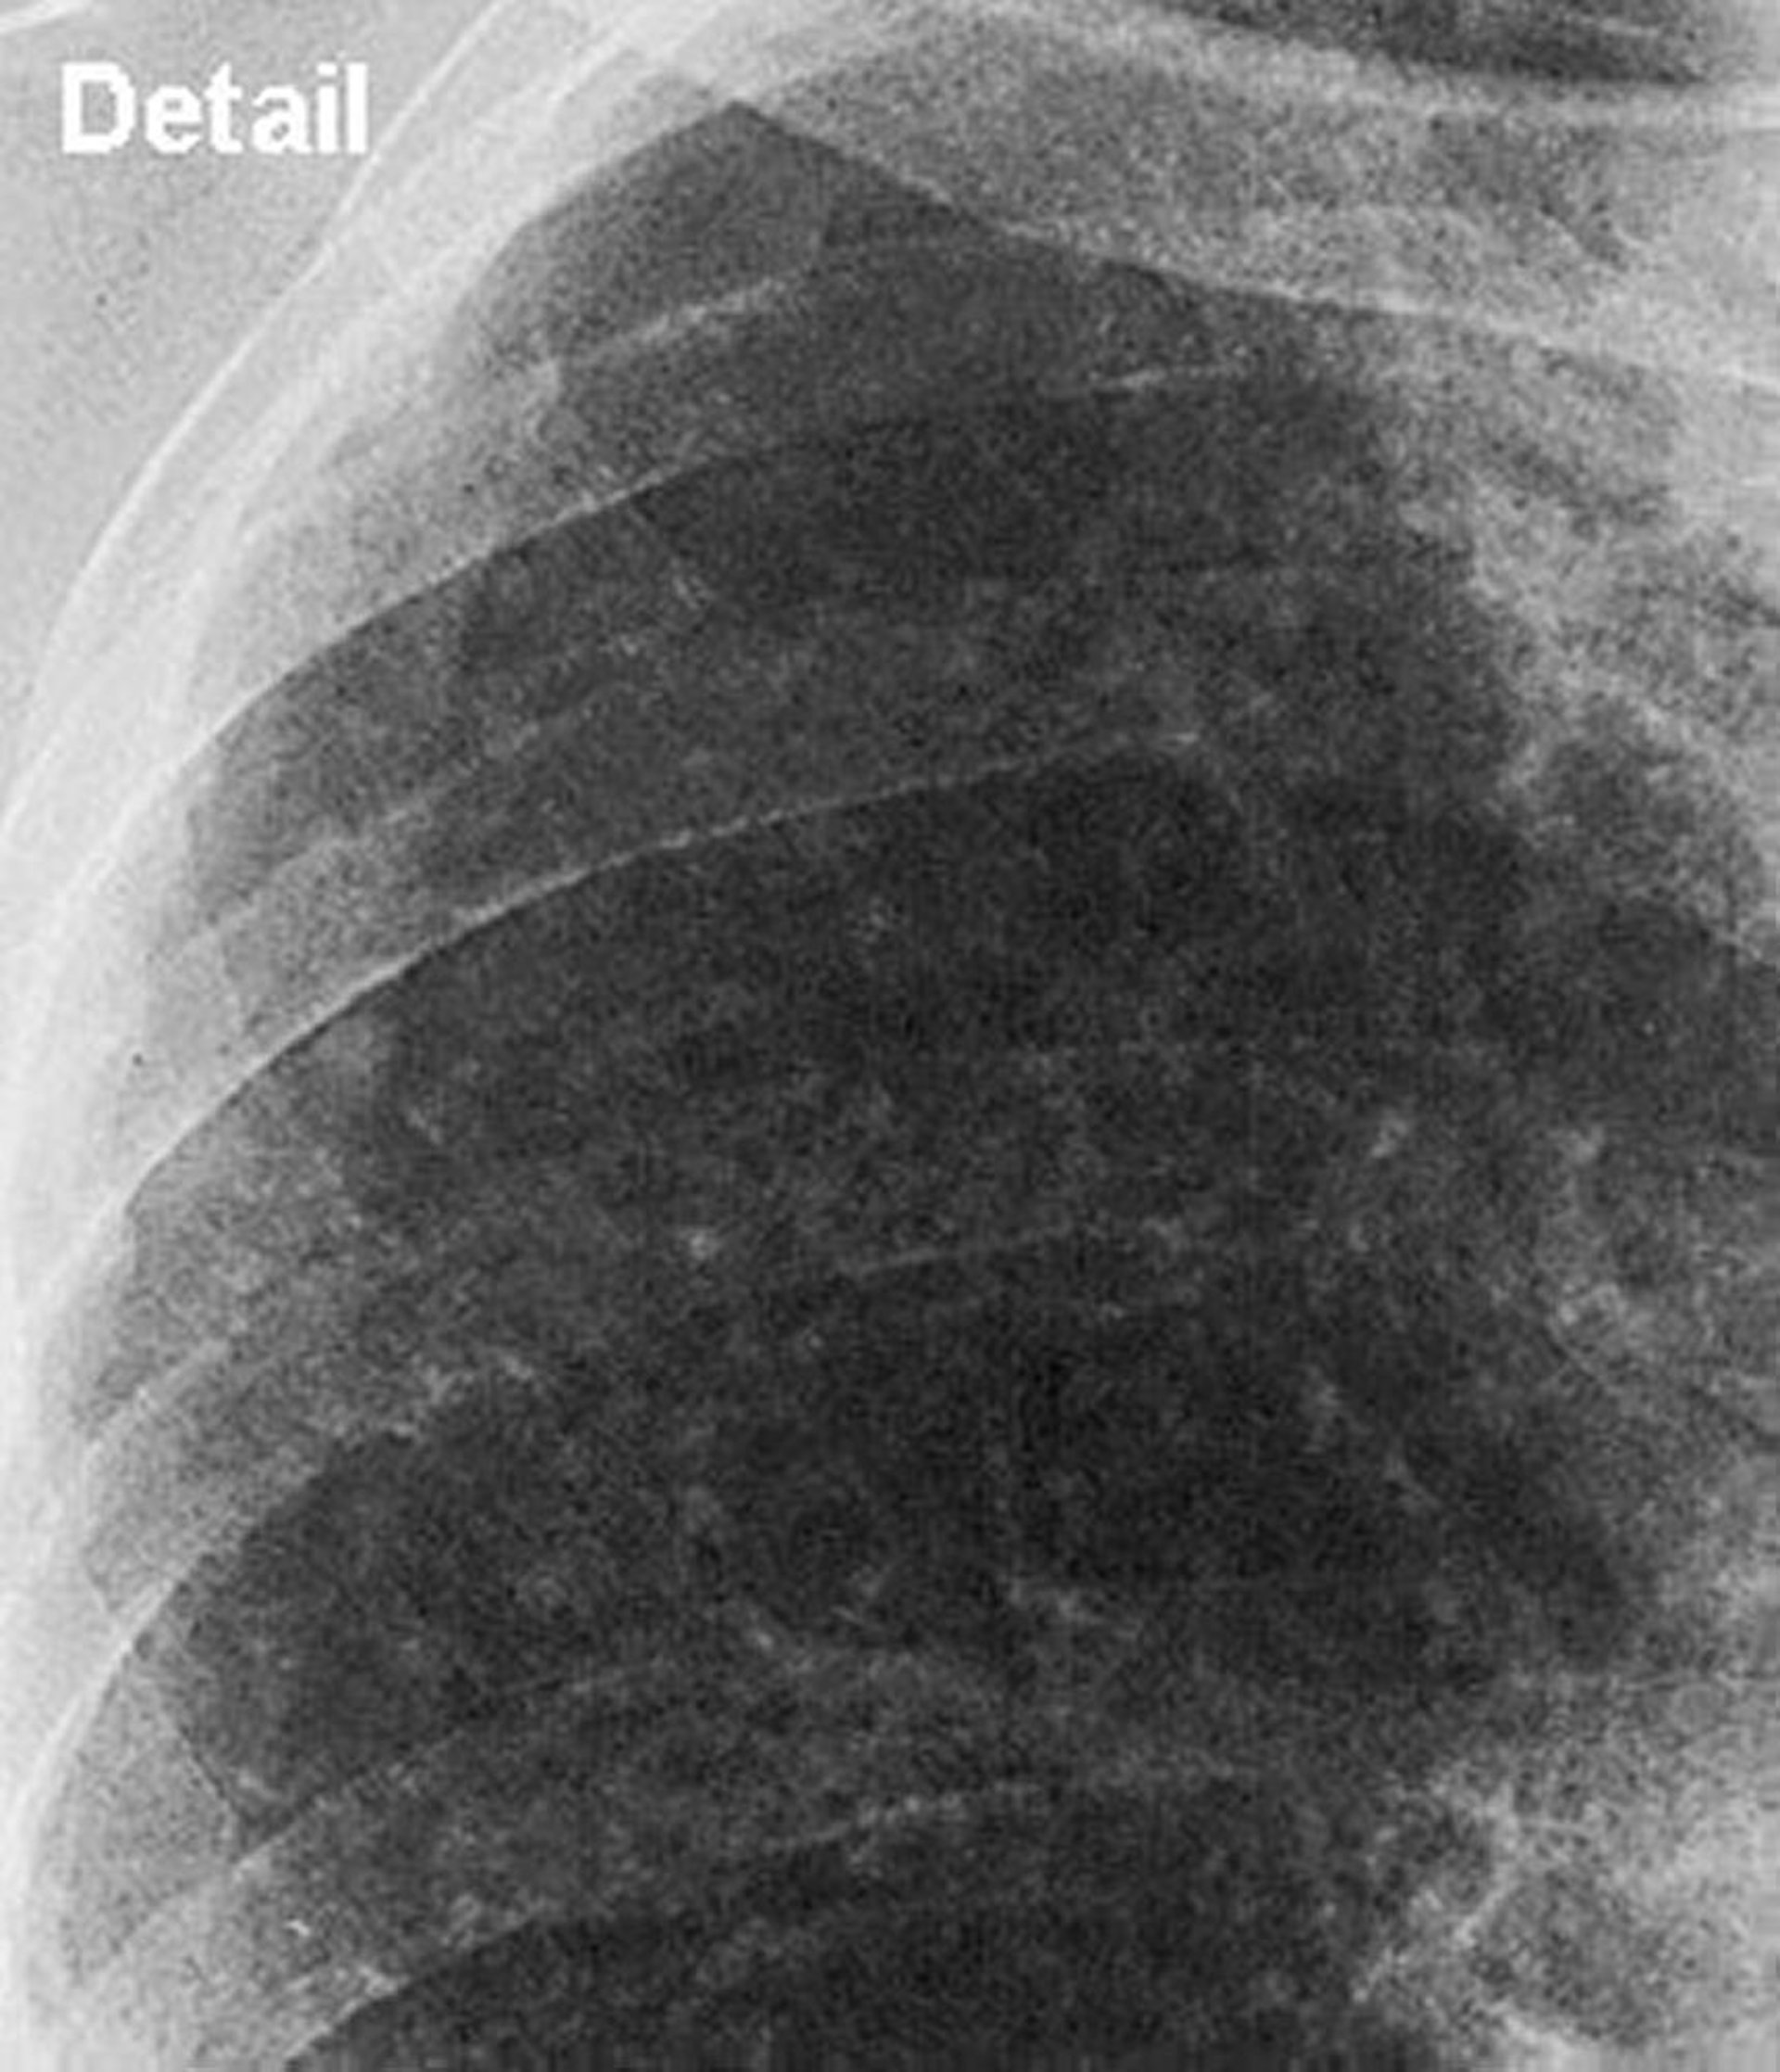

Silicosis—Simple (Upper Lung Field)

Close up view of upper lung field in simple silicosis.

Image courtesy of David W. Cugell, MD.